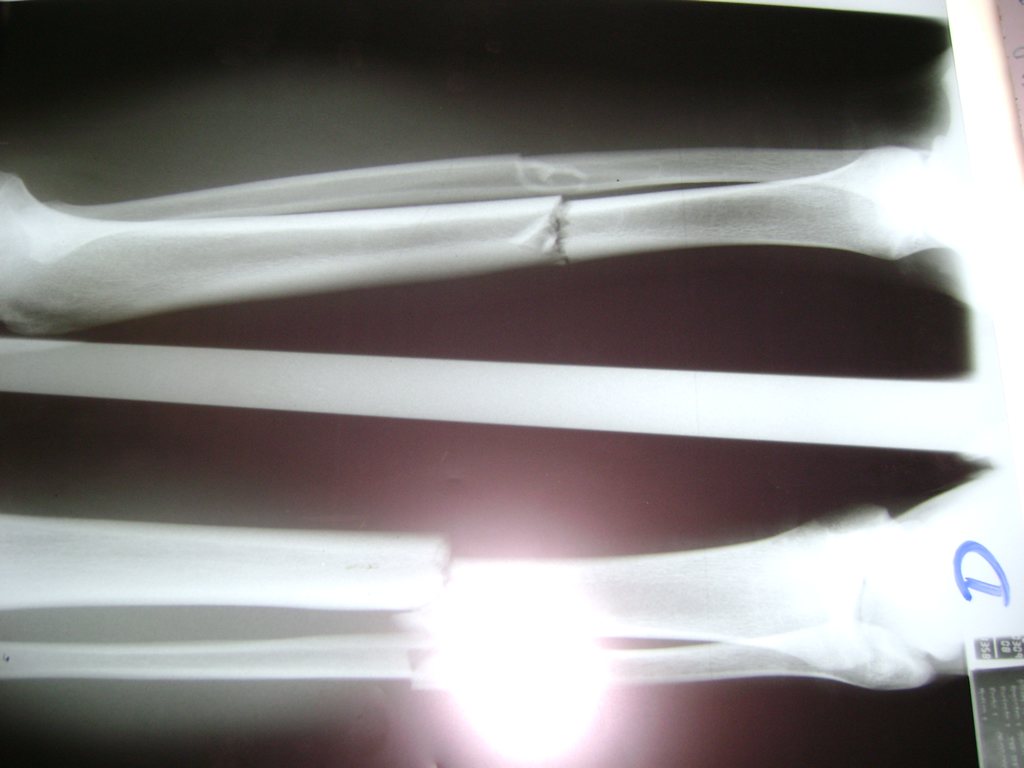

Cirugías de Codos - Perone y Tibia

Aunque cada uno de estos huesos puede fracturarse por separado, normalmente la rotura es una lesión que se produce de forma conjunta

La mayor parte de las roturas implican a la parte proximal del hueso (parte del hueso próximo a la rodilla) o a la parte distal (parte del hueso cerca del tobillo).

Debido a la fina cobertura de piel que recubre la tibia y el peroné, las fracturas generalmente son abiertas, es decir, el hueso roto rasga la piel, atravesándola. Las fracturas de tibia y peroné generalmente se producen por un fuerte impacto o torsión.